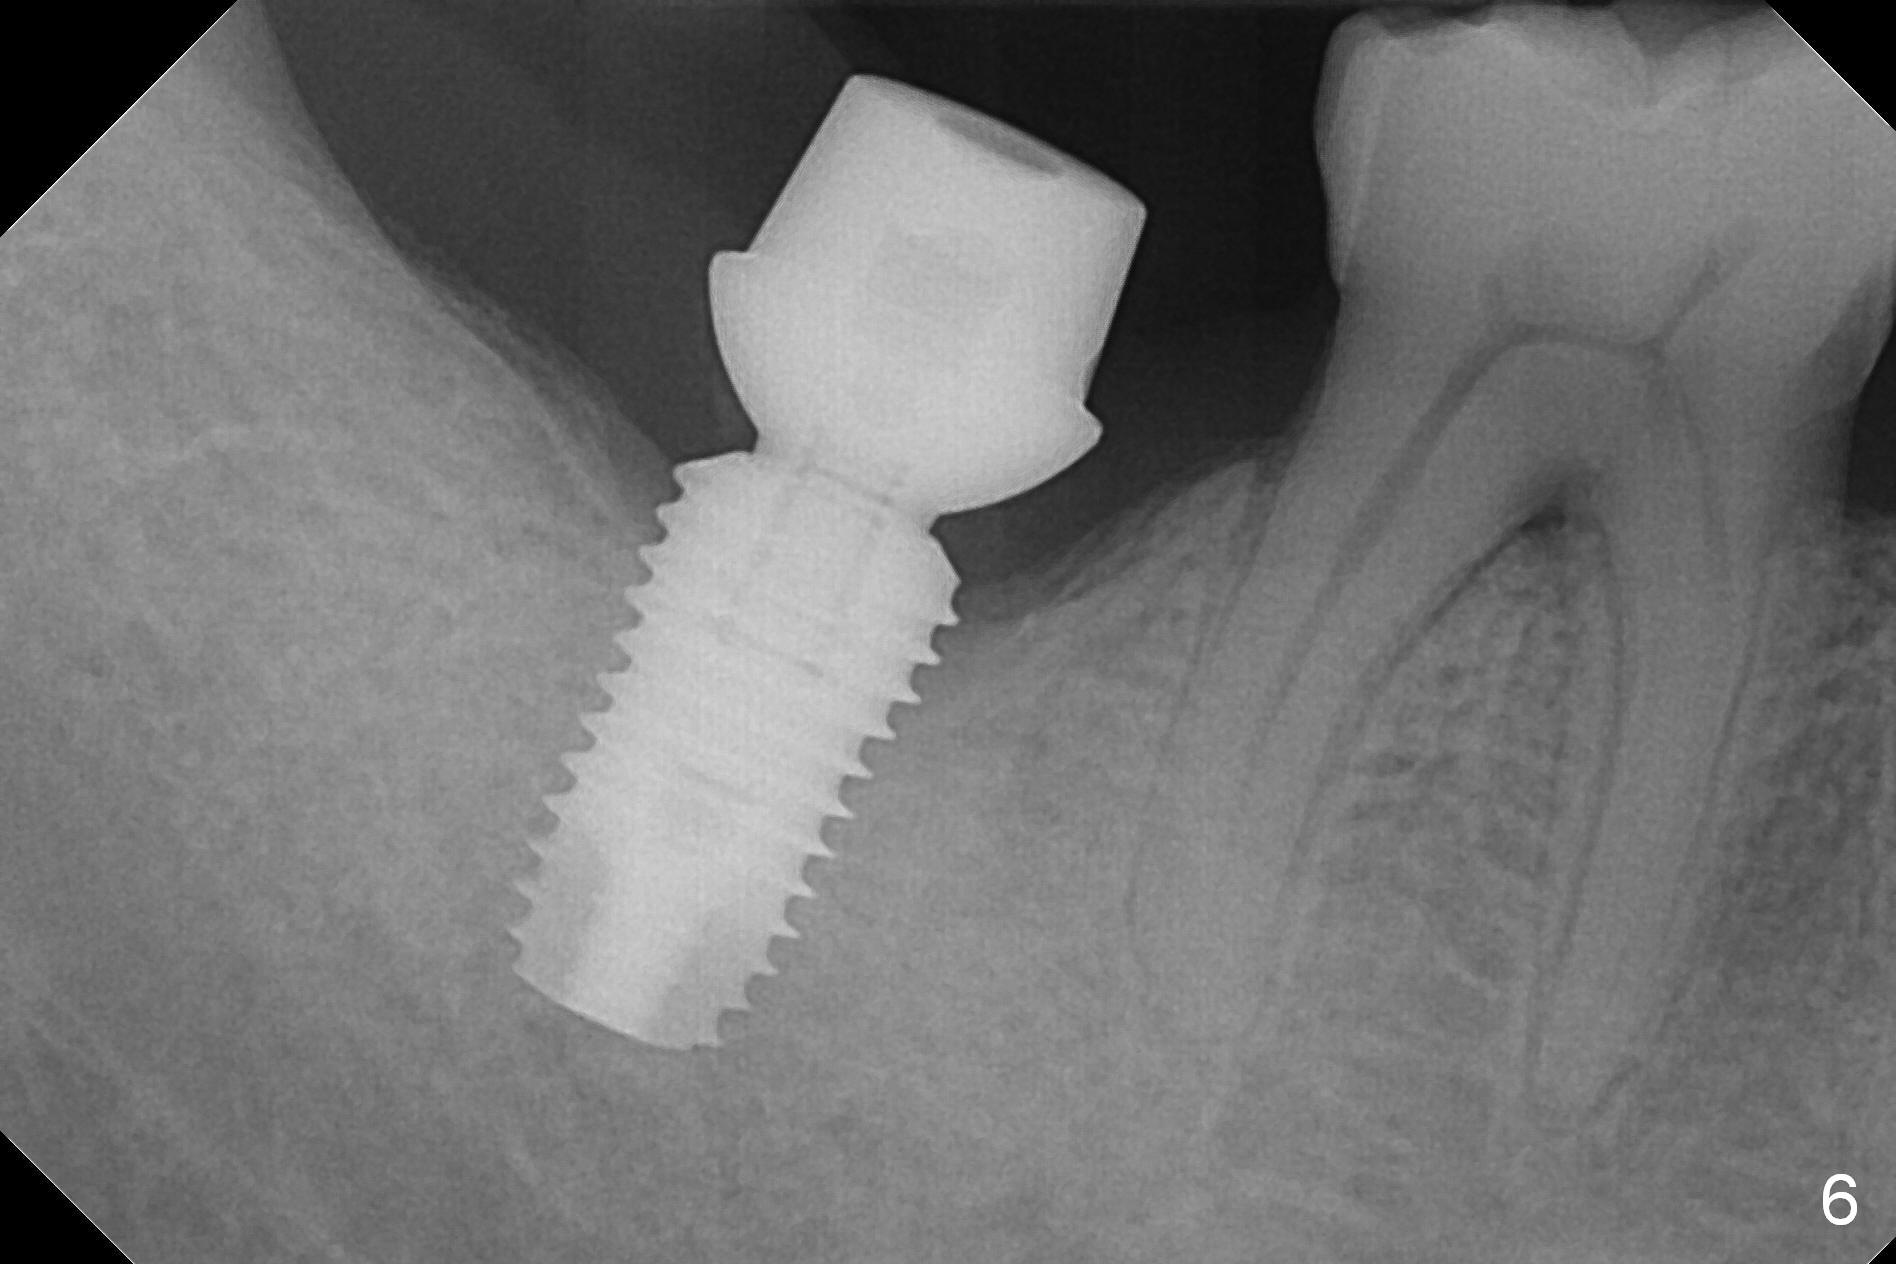

The 61-year-old man is nervous about dentistry. When he returns for #4 implant, he wants an implant at #31 first. Fig.1 shows #31 crown fracture after root canal therapy. Three years after crown placement, there is sign of mesial root fracture (Fig.2 arrowheads). Four years post extraction, bone height is 12 mm (Fig.3 parallel pin 10 mm). An extra wide implant is to be placed, since there is enough bone width. With infiltration anesthesia, the patient feels pain when a 5.4x10 mm drill is being used, 1 mm short of the desirable depth (Fig.4). After Inferior Alveolar Nerve block, the last drill reaches the depth. A 5.9x10 mm implant is placed with insertion torque 50 Ncm (Fig.5 I). A 7.8x4(3) mm cemented abutment (A) is placed immediately. After suturing, the restorative portion of the abutment is covered by the gingiva. It is probably due to over tightening the sutures. It would be ideal to adjust the gingival level before tightening the second suture.

The implant appears to have osteointegrated 8 months postop (Fig.6). The bone loss is minimal 1 year 3 months post cementation (Fig.7) and 1 year 10 months post cementation (Fig.8).